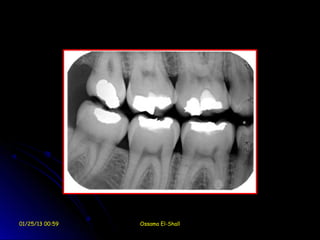

Bitewing Film

Interproximal Caries

Alveolar Bone Involvement

01/25/13 00:59   Ossama El-Shall

Overhanging amalgam filling

1.    Detection of initial proximal caries.

2.    Detection proximal overhanging margins of

fillings and crowns.

3.    Approximate estimation of the size of the

pulp chamber and pulp horns.

4.    Detection of initial interproximal crestal

alveolar     bone     resorption    indicating

periodontal disease.

5.    Determination of the position of permanent

forming teeth in relation to deciduous

ones.

6.    Determination of any proximal calculus

formation.